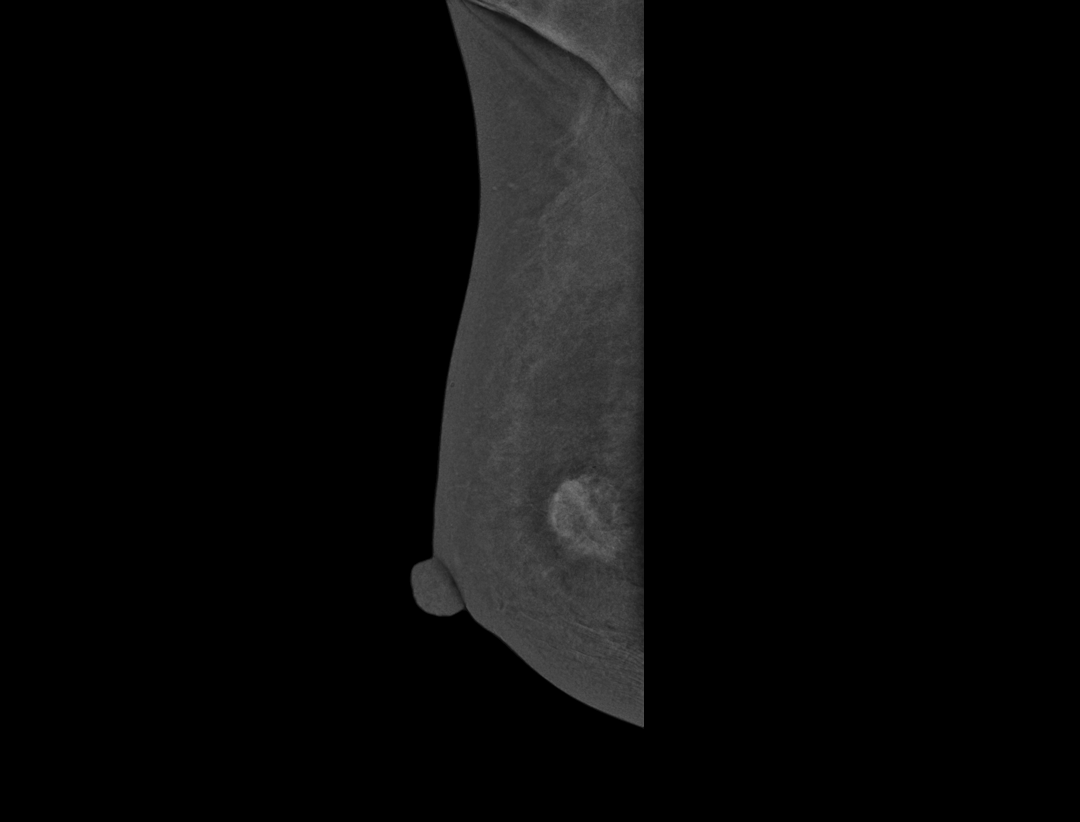

对比增强技术

7分钟排除隐患,

告别“漫长等待”